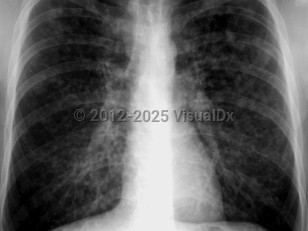

Chest radiograph changes that can be seen include interstitial changes and nodular infiltrates.